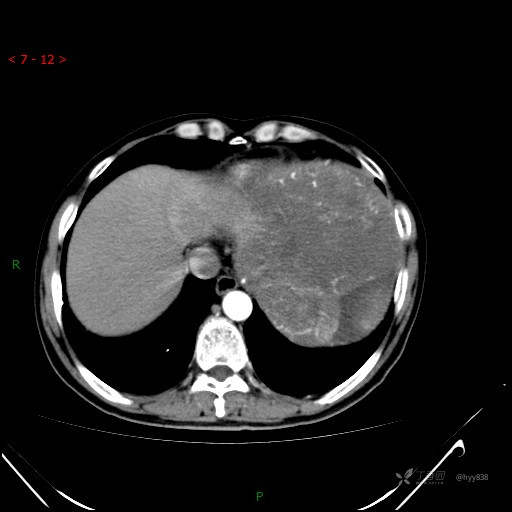

腹部CT平扫